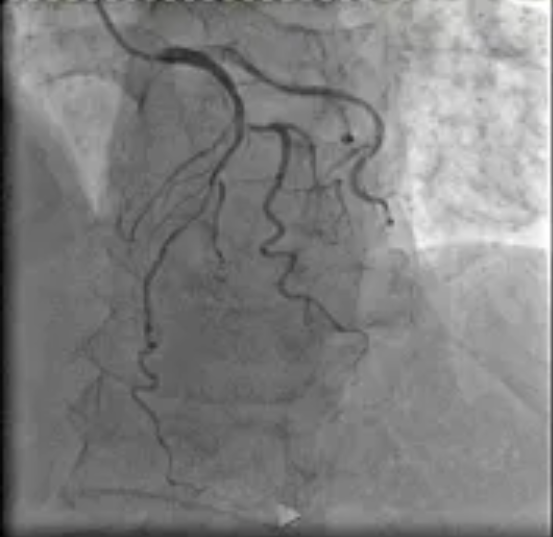

在医院心血管内科主任李昌教授的指导下,阳逻院区心内团队运用冠状动脉血管内超声(IVUS)技术详细检查患者血管,发现主支血管狭窄程度处于临界状态,可暂时通过药物治疗来优化;分支血管严重狭窄,需要进行介入治疗。基于IVUS提供的精准信息,患者避免了不必要的支架植入,有效降低手术风险。这一精准化治疗方案,既减少患者创伤与经济负担,又降低术后并发症风险,为患者的健康提供了有力保障。

患者IVUS检查影像报告